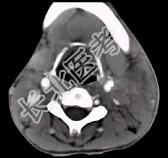

- 单项选择题男性,67岁, 颈部出现疼痛性肿块半年余,CT扫描如图所示, 最可能的诊断是 ( )